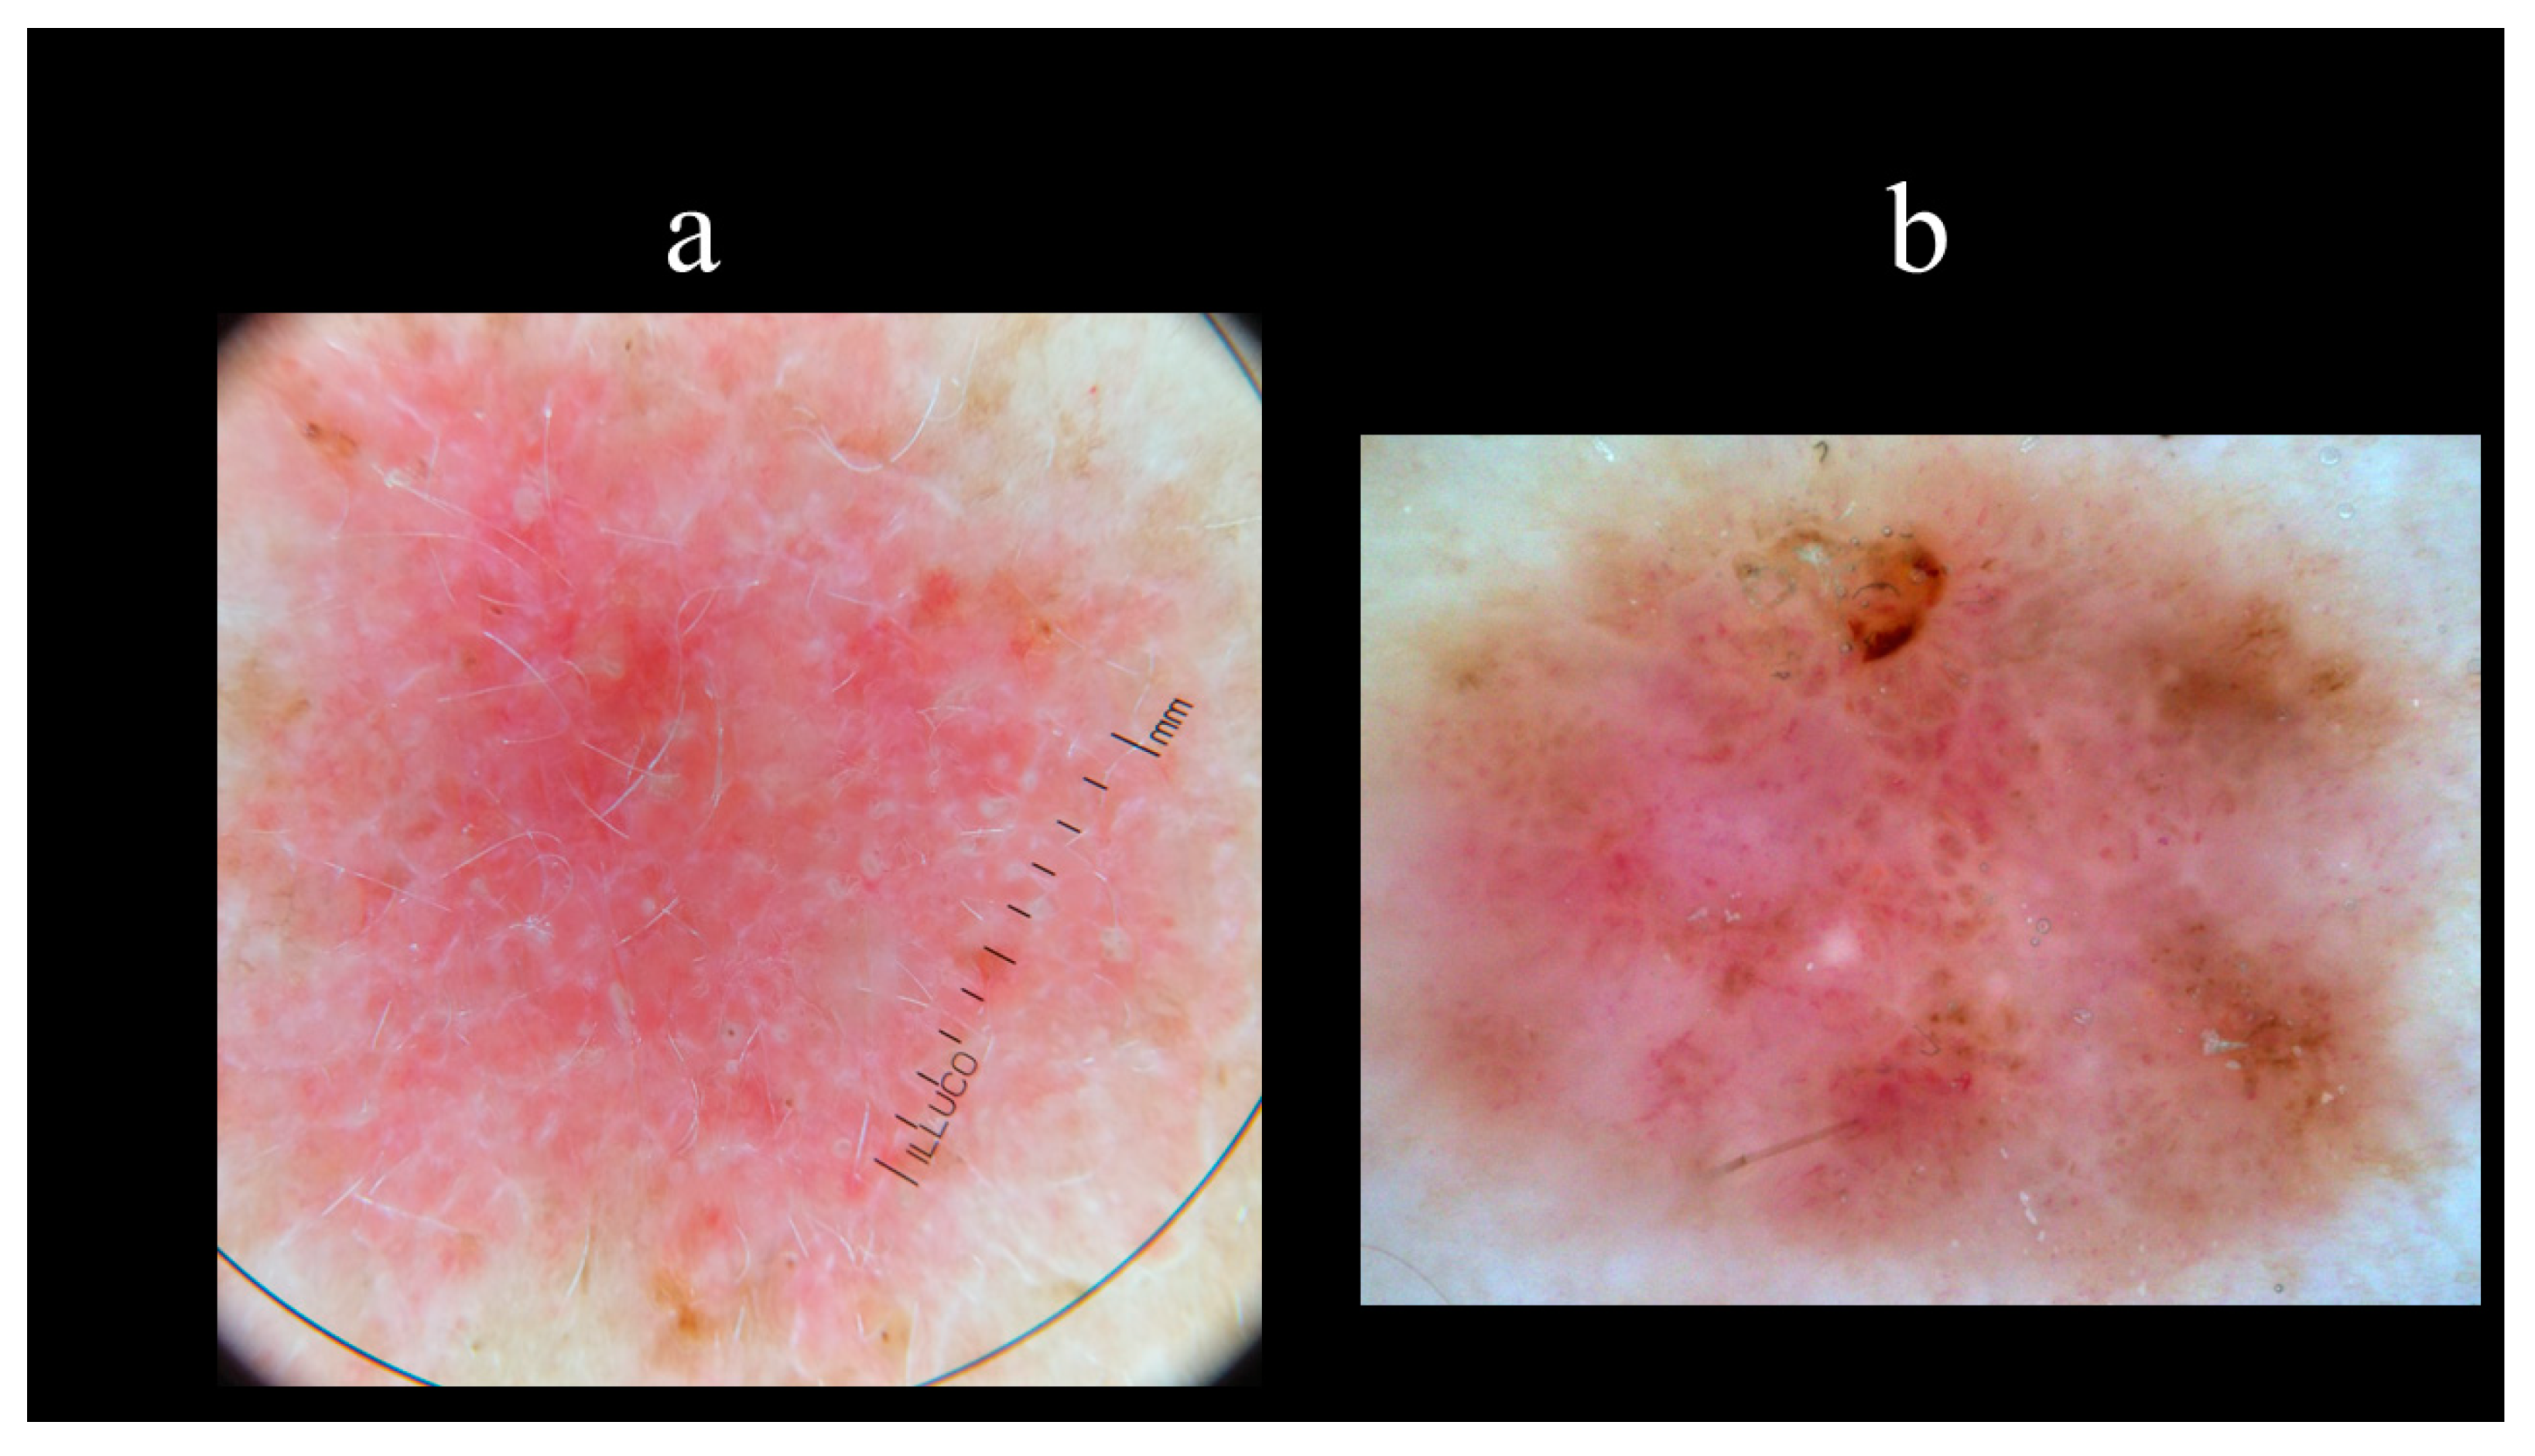

5. Dermoscopy

8.5. Photodynamic Therapy (PDT)